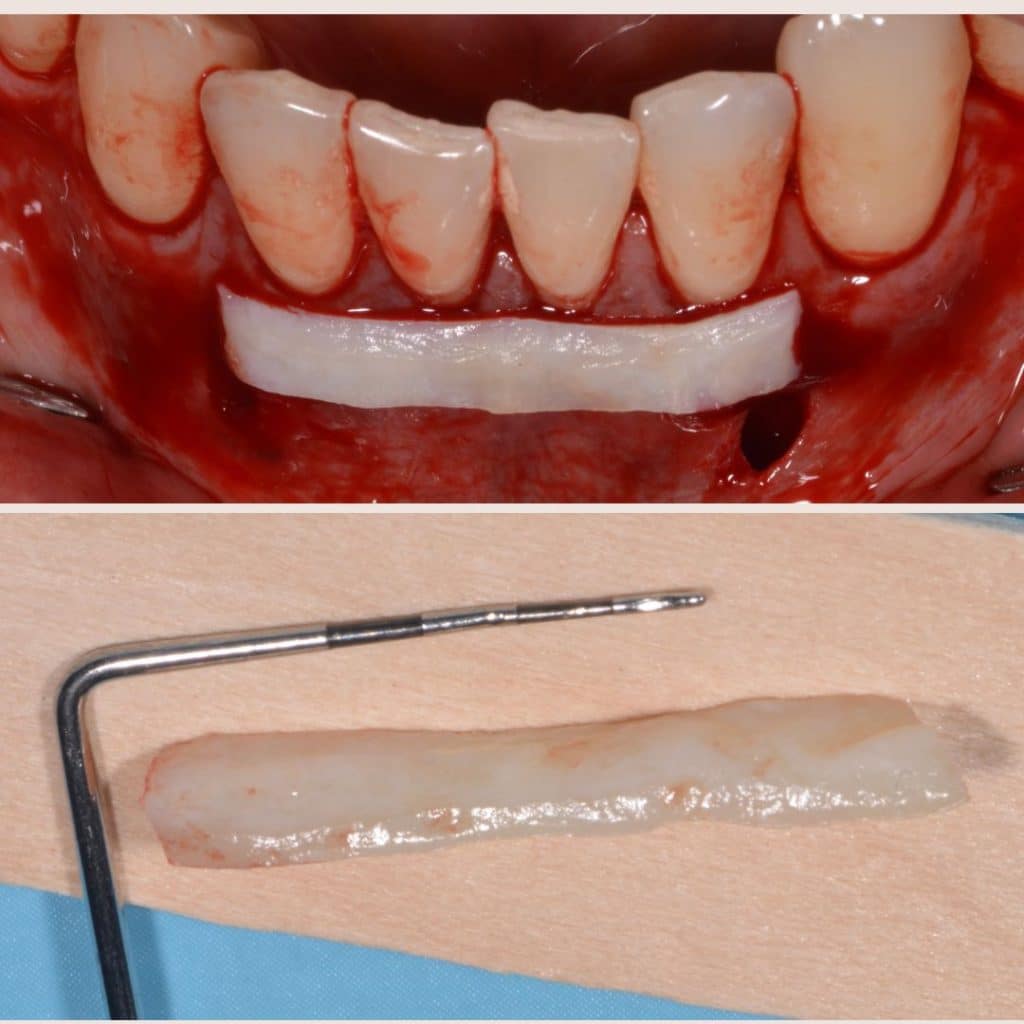

This patient presented with Miller Type III recessions (Cairo’s RT2) with a thin gingival biotype in all four lower incisors. In this case, we opted for a VISTA technique and a connective tissue graft (free de-epithelialized) for its resolution.